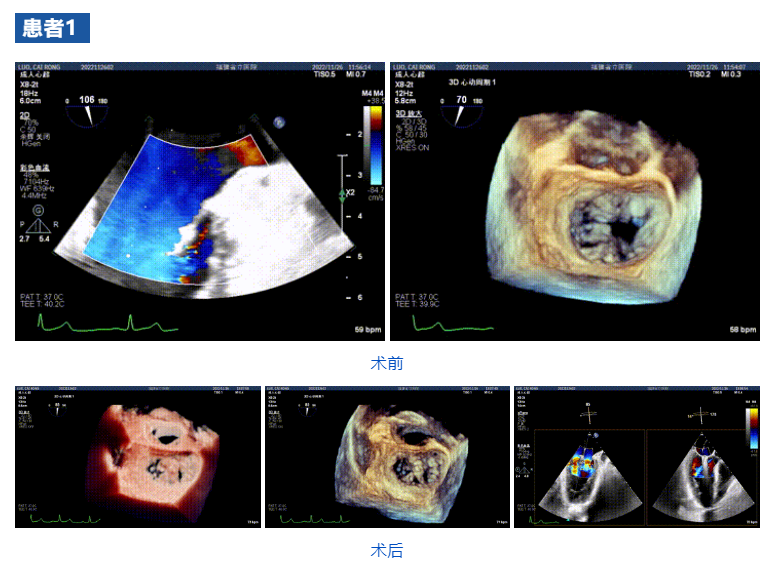

接受治療的三例患者均為器質性重度二尖瓣反流(DMR)患者,術前超聲提示二尖瓣后葉脫垂伴4+反流,左室舒張功能減退。郭延松教授攜同團隊成員陳新敬副教授和洪景宣、方明程、楊清勇主治醫(yī)師、心外科丁杭主任以及超聲科賴寶春、葉振盛主治醫(yī)師共同進行病情討論。考慮到患者高齡、基礎疾病多、STS評分高,為外科手術極高?;颊?,不適合進行外科開胸二尖瓣手術,因此決定為患者實施經導管緣對緣修復介入術(JensClip經導管瓣膜夾系統(tǒng))。

在浙江大學醫(yī)學院附屬第二醫(yī)院王建安教授團隊的支持下,手術經股靜脈-房間隔入路,采用全身麻醉插管,在TEE和DSA引導下完成房間隔穿刺。置入JensClip瓣膜夾系統(tǒng)后,在左房調整瓣膜夾的位置和軸向,后進入左室,在TEE引導下捕捉二尖瓣前后瓣葉,并關閉瓣膜夾。經TEE反復確認手術效果后最終鎖定并釋放瓣膜夾。術后即刻超聲顯示瓣膜夾位置穩(wěn)定,功能良好,二尖瓣反流由術前4+減少至微量,手術圓滿成功。